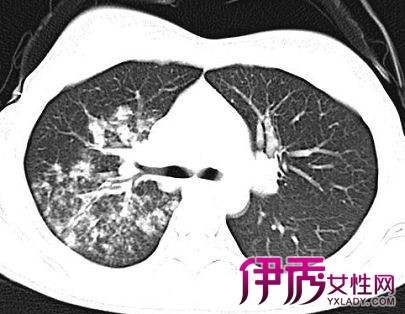

结核病是由结核分枝杆菌引起的慢性传染病,可侵及许多脏器,以肺部结核感染最为常见。排菌者为其重要的传染源。人体感染结核菌后不一定发病,当抵抗力降低或细胞介导的变态反应增高时,才可能引起临床发病。若能及时诊断,并予合理治疗,大多可获临床痊愈。